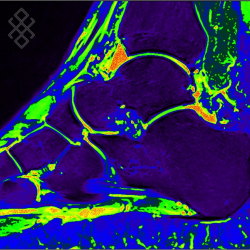

IRM de la Cheville

Vous entrez dans l'aimant, ouvert des 2 côtés, les pieds en premier et allongé sur le dos avec les bras le long du corps. Pour recueillir le signal et construire les images, vous aurez la cheville dans une antenne. Étant donné que cet examen est bruyant, vous aurez à votre disposition des tampons auriculaires pour atténuer le bruit de la machine.